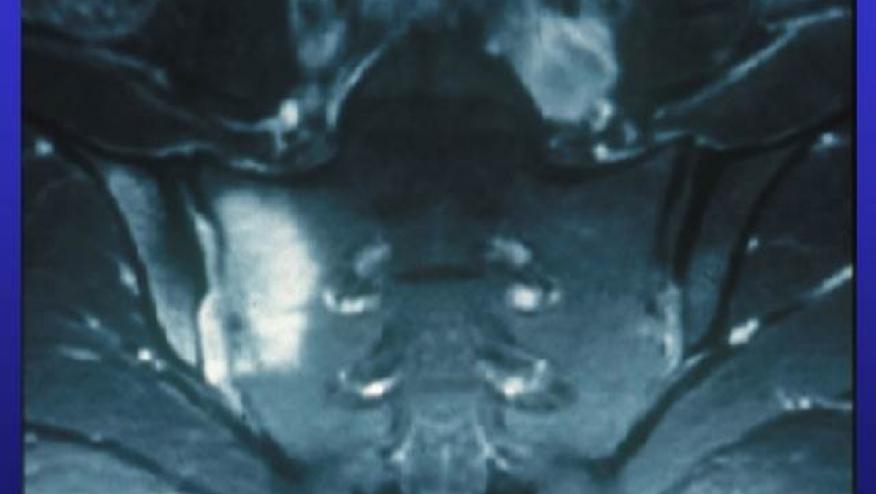

MRI was performed on a 3T machine and images were analyzed for the presence of deep bone marrow edema (BME), fat metaplasia, erosion, and new bone formation. The researchers also applied the Spondyloarthritis Research Consortium of Canada (SPARCC) scoring system, and determined whether the findings met Assessment of SpondyloArthritis International Society (ASAS) criteria for SpA positivity.

One-fifth of participants showed sacroiliac joint erosions, and 14% had fat metaplasia. Erosions were seen in nearly 40% of those 40 and older; spinal BME was also present in 36% of this age group, and 29% showed fat metaplasia. SPARCC scores for both the sacroiliac and spine correlated with age. Among the subset 45 and older, the 95% confidence intervals for SPARCC scores overlapped those for a historical cohort of 84 SpA patients.